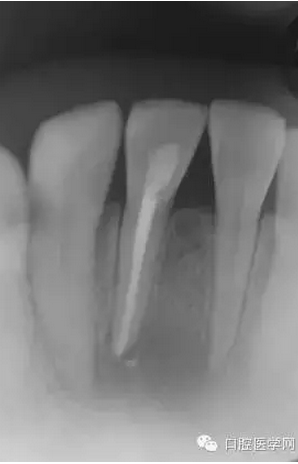

(圖 2) 根管長(zhǎng)度測(cè)定

就

診當(dāng)日進(jìn)行了開髓,測(cè)量根管長(zhǎng)度及根管成形。開髓時(shí)釋放出嚴(yán)重的惡臭,而且可以看到大量膿液通過(guò)根管流出來(lái)。當(dāng)日于唇側(cè)腫脹部位的最下端進(jìn)行了半月形切

口,使膿液從切口處流出,通過(guò)根管和切口,使用大量地生理鹽水清洗根尖病灶部位。當(dāng)天根管成形后,為防止食物塞入根管內(nèi),并便于膿液或氣體的排出,使用棉

球封住根管口。